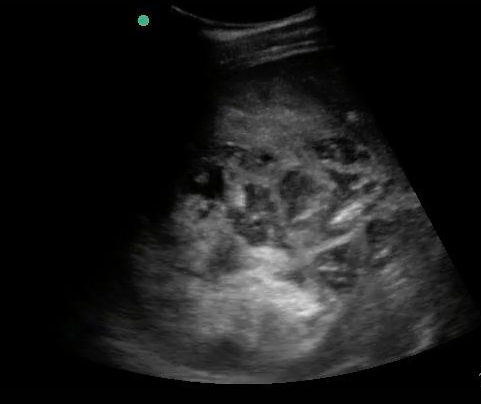

Figure 23. Axial view of liver demonstrating multifocal hyperechoic lesions due to hepatocellular carcinoma. Note the surrounding ascites.

- A large dominant lesion with smaller “satellite” lesions is typical, but not sensitive.

- Often hypervascular and may invade hepatic vasculature.